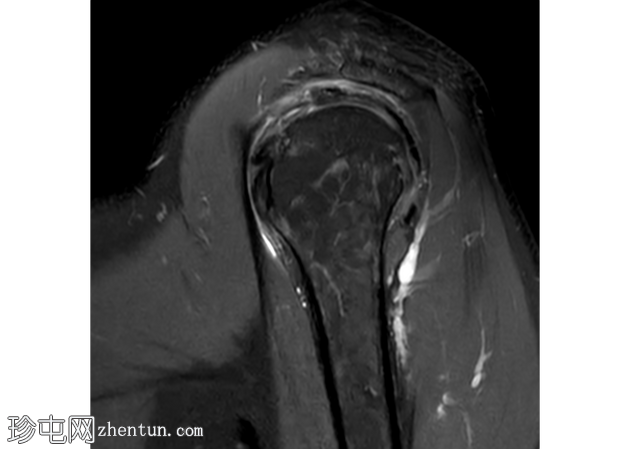

轴向

PD

冈上肌腱滑囊侧存在部分厚度撕裂,肌腱物质内分层延伸约2厘米,与滑囊侧分层部分厚度撕裂相符。伴有间质性肩胛下肌腱(SST)撕裂。冈上肌体积轻度减少。

冈下肌腱、小圆肌腱和肩胛下肌腱完好,无明显撕裂迹象。

冠状面可见盂唇上方T2高信号,提示SLAP损伤。SLAP损伤延伸至肱二头肌长头,矢状面清晰可见。肱二头肌长头腱正常位于肱二头肌沟内,周围积液极少。

肩胛下肌隐窝和喙突下滑囊内有少量积液。

轻度肩锁关节病,特征为轻度肥大、少量关节内积液和微量肩峰下积液。

轻度盂肱关节积液。伴有肩关节囊增厚和水肿,提示反应性关节囊炎。

未发现骨髓水肿或骨折。